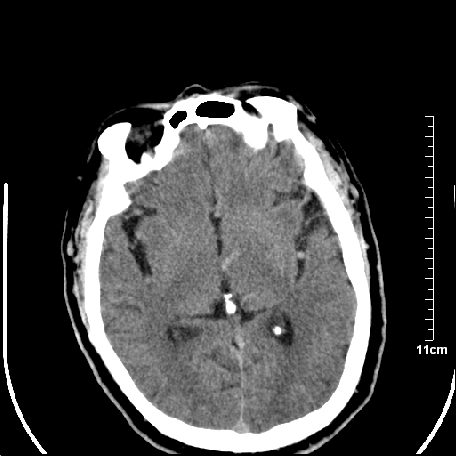

外伤患者,什么病,

外伤患者,没什么症状,

双侧外侧裂,左侧脑沟见高密度结节影,边清,还有鞍上池层面密度也高

都是血管。

脑血管硬化?高血红蛋白症?

高血红蛋白症可能

高血红蛋白症

高血红蛋白血征

基底动脉硬化迂曲。高血红蛋白血症。